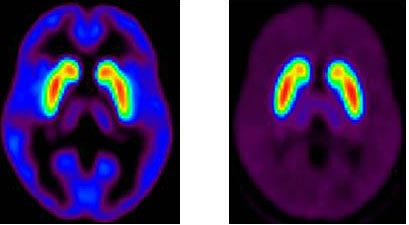

脳内イメージング

土曜に放射線医学総合研究所(放医研)のS先生の講演を聞きました。最近のPET(Positron Emission Tomography)研究(今回は統合失調症に対する)もので、生体内(脳内)で起きていることを画像化している研究で面白かったです。僕も一時期少しばかり研究というものをしたことがあります。被検者の方々の血液を採取して血小板を使ったものですが、やはり「人体内で起きていることと同じことなのか?」という疑問は常にありました。それが今回の発表を聞くと、脳内で起きていることを可視化できるようになりつつあることが良く分かりました。脳の研究は今後も重要分野です。科学者の皆様には頑張ってもらいたいですね。